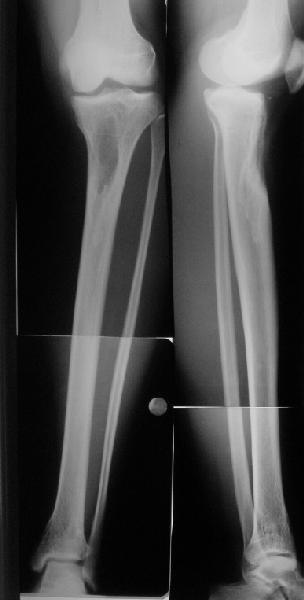

Коллеги из детского отделения направили 18-летнюю студентку с варусно-рекурвационной деформацией проксимального отдела голени.

Жалобы у нее на появившиеся боли в колене при нагрузках. Признаков воспаления не было и нет, опухолевого роста также. Природа дефекта в области бугристости не очень понятна. Дополнительно сделали КТ и боковой снимок в максимальном разгибании - все в приложении.

По-поводу деформации - Вы имеете дело с епи-метафизарной деформацией, скорее всего по причине преждевременного частичного закратия проксимальной зоныы роста большеберцовой кости.

Рекурвации в коленном суставе нет, есть рекурвационная деформация проксимальной части голени.

Для точных расчётов необходимо сделать снимки двух ног прямые и боковые на всю длину от тазобедренных суставов до стоп.

Ориентировачно на боковой проекции угол между тибиальным плато и анатомической осью тибии на передне-боковой проэкции должен быть порядка 90 градусов, а на боковой 80, кроме того на боковой проэкции при выпрямленном колене передний кортекс большеберцовой кости должен находиться на одной линии с передним кортексом бедренной кости.